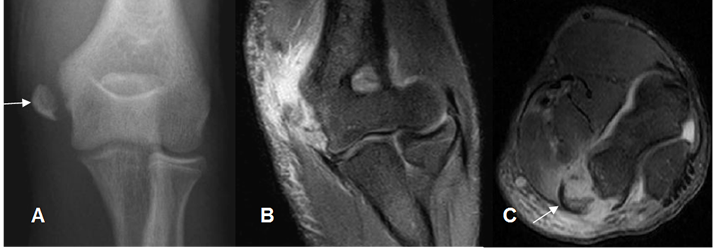

Fig 37 C. Avulsión.

A: Rx AP, B: RM coronal en STIR y C: RM axial en STIR. Avulsión del epicóndilo medial, con cambios inflamatorios en los tejidos blandos.